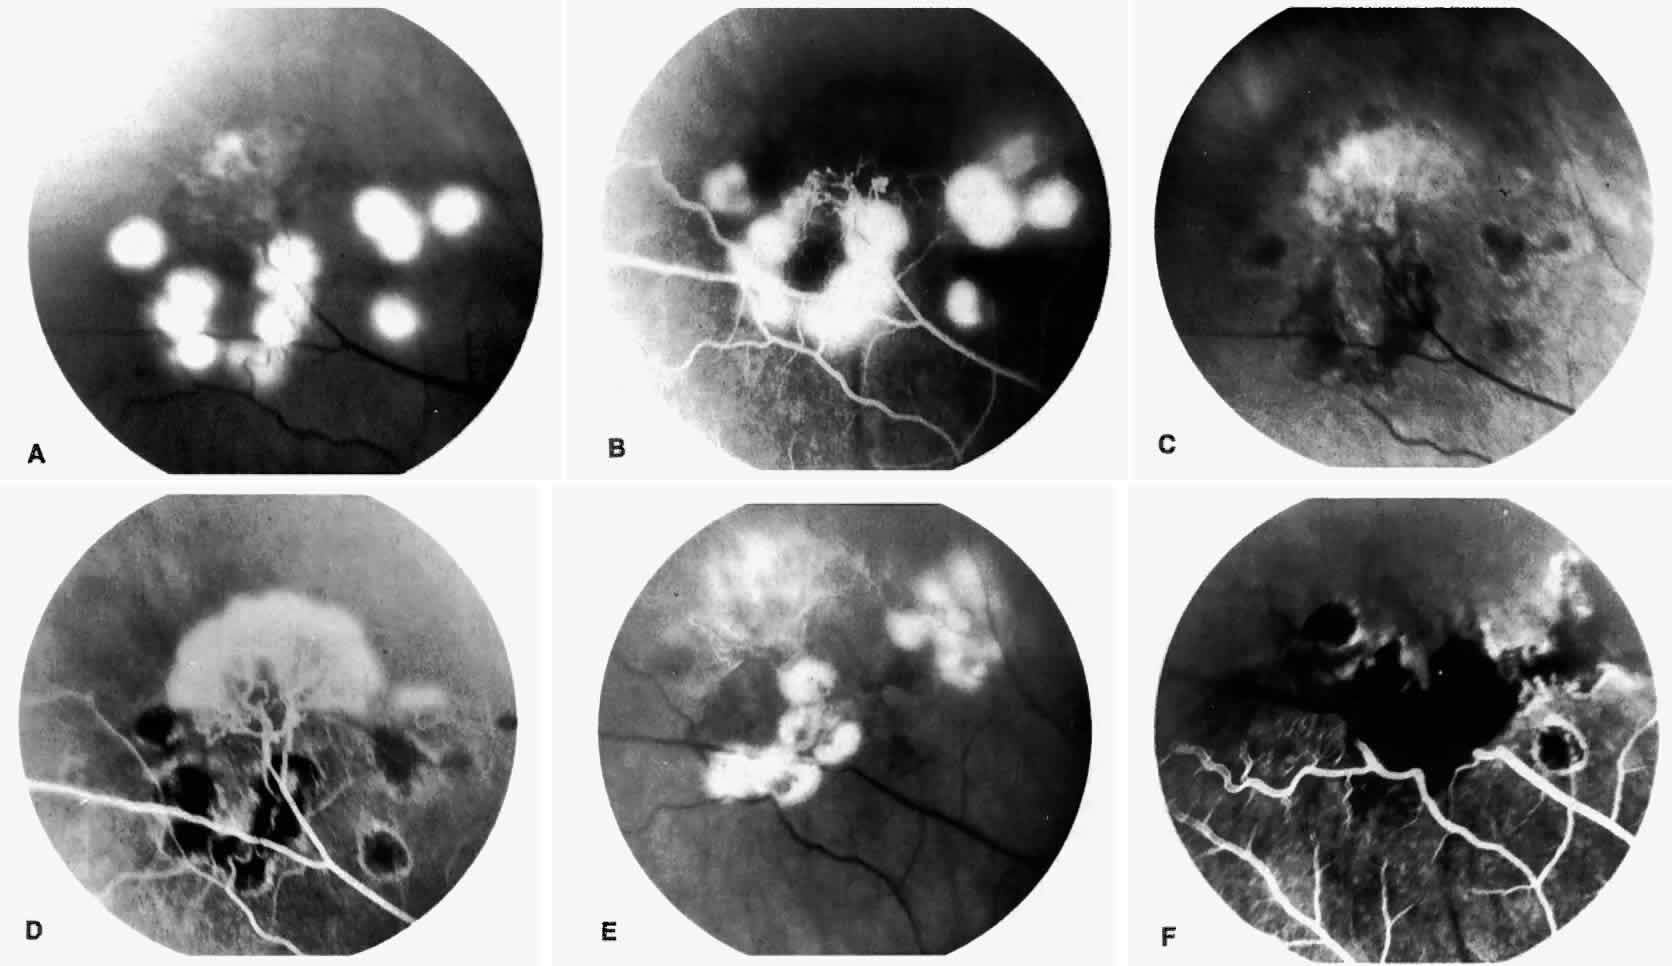

STAGE III: PRERETINAL NEOVASCULARIZATION (PROLIFERATIVE SICKLE RETINOPATHY). “Sea fan”-shaped neovascularization typically develops on the venular side of an arteriolar-venular anastomosis, mimicking the normal development of retinal capillaries (Fig. 24).125 A lowered oxygen tension and angiogenic factors released on the venular side may be the stimulus for neovascular growth.125,126 In most instances, the direction of growth is toward the ora serrata, from the perfused retina toward the nonperfused retina. Presumably, this represents an abortive attempt to revascularize the nonperfused retina, initiated by vasoproliferative factors.

The characteristic neovascular lesions of PSR are called sea fans because they resemble the marine invertebrate Gorgonia flabellum.70 They tend to occur more commonly in the temporal periphery, but they have been reported to occur in the temporal macula in the presence of extensive nonperfusion.130,133 Initially they grow on the surface of the retina, but they often become elevated into the vitreous and adhere to a partially detached posterior hyaloid.114 It may be difficult to visualize small sea fans ophthalmoscopically; however, fluorescein angiography clearly demonstrates leakage of dye into the vitreous (Fig. 25). The feeding arteriole is usually more tortuous than the draining venule (Fig. 26). Early on, the neovascular lesion is fed by a single arteriole and drained by a single venule, but with time, additional arterioles and venules become arborized within the lesion (Fig. 27).129 Growth of the sea fan often occurs circumferentially, rather than radiallyÜmh- 1Ý, toward the ora serrata. Progressive circumferential growth may lead to neovascular lesions extending around the entire periphery. As it matures, a white fibroglial mantle often covers the neovascular tissue (Color Plate 2B).

PSR is associated with the severe vision-threatening sequelae of sickle cell disease: vitreous hemorrhage (stage IV) and retinal detachment (stage V). These stages are believed to result from transudation of blood components into the vitreous through the incompetent neovascular tissue (Fig. 28). Vitreous fluorophotometry has quantified the leakage from the peripheral neovascularization.134 This leads to premature syneresis and collapse of the vitreous, inducing tractional forces on the retina that lead to vitreous hemorrhage, retinal tears, and tractional and rhegmatogenous retinal detachment. In rare cases, an exudative detachment may occur.

Spontaneous nonperfusion or autoinfarction, accompanied by regression of the neovascular lesion, occurs in 20% to 60% of eyes with PSR.135,136 The peak incidence of autoinfarction is 2 years after the development of PSR. It appears that autoinfarction occurs primarily as a result of (1) occlusion of the feeding arteriole due to traction on the neovascular lesion by contracting vitreous, or (2) occlusion by sickled RBCs. The latter probably is more common in homozygous sickle cell anemia, which is more commonly associated with autoinfarction and complete vascular occlusion.

STAGE IV: VITREOUS HEMORRHAGE. Vitreous hemorrhage often complicates PSR. In a selected series of patients with untreated SC disease, vitreous hemorrhage was found in 28% at diagnosis and in 44% after 31 months.130 In the presence of neovascularization, the three risk factors for the development of vitreous hemorrhage include SC disease, more than 60° of perfused sea fans, and the presence of old blood in the eye.139 In a long-term follow-up of an untreated control group participating in a randomized clinical trial of feeder vessel photocoagulation for PSR, vitreous hemorrhage occurred in 45% of eyes and was recurrent in two thirds of these eyes.140

Transudation of plasma results in vitreous syneresis and fibrosis and induces collapse of the formed vitreous, which causes traction on the adherent neovascular tissue. The fragile elevated vessels in the neovascular membranes are prone to rupture, resulting in hemorrhage.141 The hemorrhage is frequently localized in the periphery near the sea fan, but diffuse hemorrhage does occur and may obscure fundus details (Color Plate 2C).